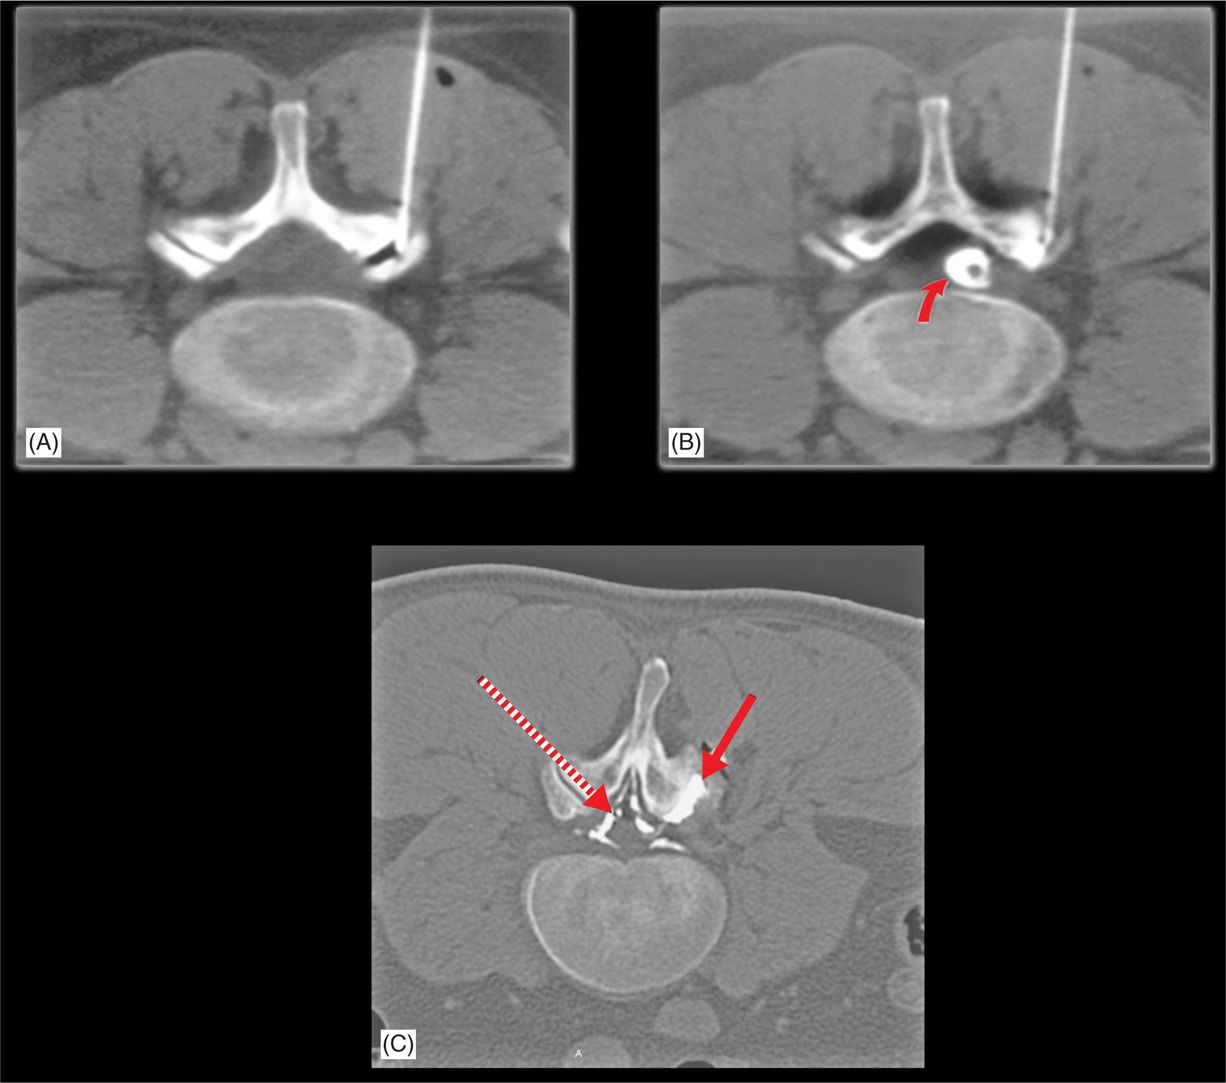

Relationship between facet joint opening on CT and facet joint effusion

Measurement of the facet joint effusion and facet joint width. A Facet Effusion Definition A diagnostic positive facet joint block can indicate facet joints as the source of chronic spinal pain [], but the rate of false positives remains high. Identify the etiology of facet joint disease. The term “segmental instability” of the lumbar spine is not clearly defined, especially as it relates to degenerative spondylolisthesis. Symptoms and diagnosis of facet joint disorders. Evaluate. Facet Effusion Definition.

Relationship between facet joint opening on CT and facet joint effusion Facet Effusion Definition Lumbar facet joint disorders most commonly cause lower back pain that is. Larry parker, md, orthopedic surgeon. The term “segmental instability” of the lumbar spine is not clearly defined, especially as it relates to degenerative spondylolisthesis. The facet pain syndrome from osteoarthritis is suspected from a patient’s history (referred pain pattern) and physical. Evaluate the treatment and management options available.. Facet Effusion Definition.